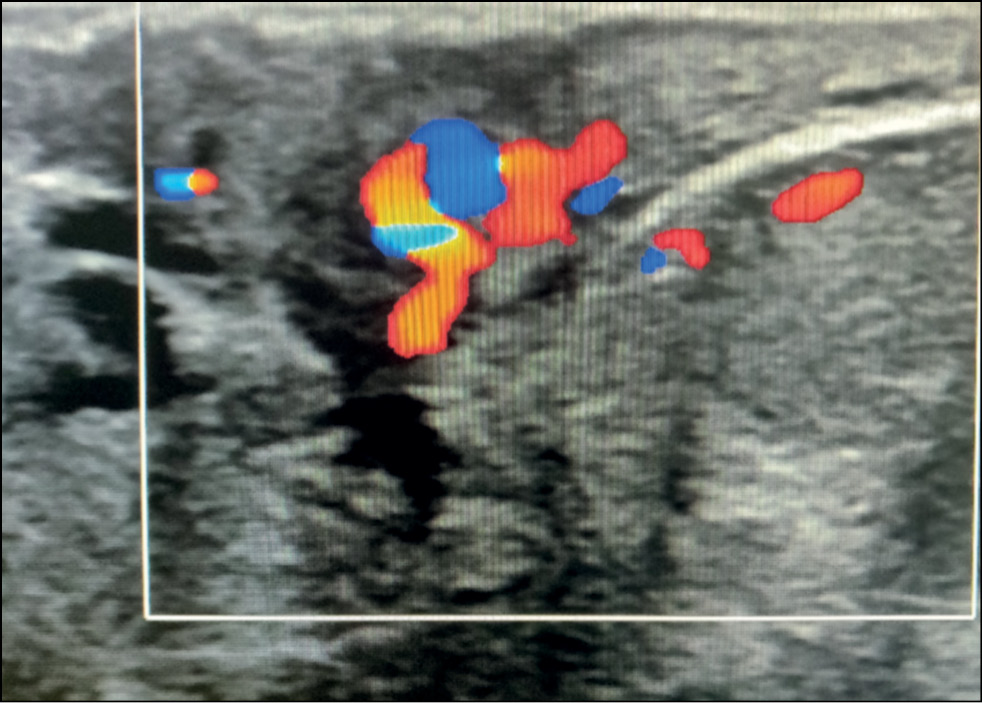

A 59-year-old patient complained of erosive changes in the nipple (Fig. 1). Physical examination revealed erythema, erosion, and nipple retraction. Doppler ultrasonography with color flow mapping revealed increased blood flow in the nipple projection (Fig. 2). Mammography findings were normal. To assess the extent of disease spread, breast MRI with contrast enhancement was performed. The early postcontrast series (Fig. 3) and maximum intensity projection (MIP) images (Fig. 4) showed a segmental contrast retroareolar area from the nipple level to posterior breast sections. Ultrasound-guided core biopsy followed by immunohistochemical analysis revealed Paget’s disease of the nipple with high-grade intraductal carcinoma in situ. Receptors for estrogen (G3 ER) and progesterone (PR) were negative. Oncogenic protein Ki-67 was 45%.

Figure 2. Paget’s disease: increased blood flow on color Doppler imaging.